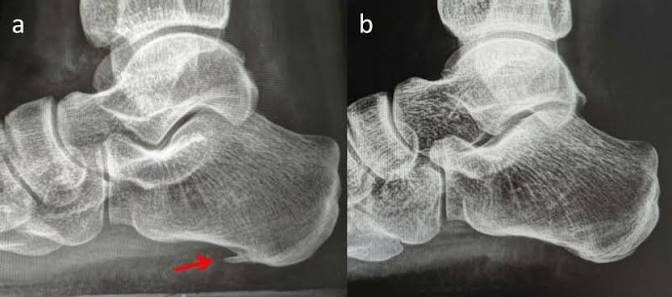

What is more likely to happen from heel smashing are bone spurs. Bone spurs are abnormal sharp protrusions of bone from an existing bone. Bone spurs can tear up your tissues from the inside.

Heel smashing will also just cause bruising and severe damage to the tissues in you heel over time. Severe tissue injury can result in necrosis.